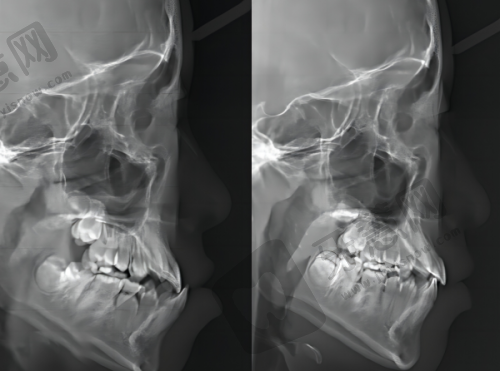

牙齿矫正:包括传统金属矫正、隐形矫正等多种方式,医生会根据患者的具体情况制定个性化的矫正方案,让牙齿排列更加整齐美观。